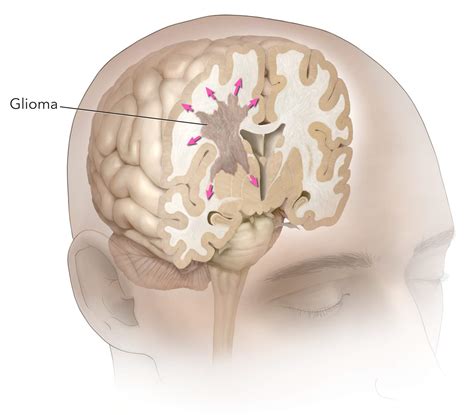

A diagnosis of a High Grade Glioma is a life-altering event that brings with it a complex array of medical terminology, treatment decisions, and emotional challenges. These tumors, which originate from the glial cells that support neurons in the brain and spinal cord, are categorized by their aggressive behavior and rapid growth. Understanding the nature of these malignancies is the first step toward navigating the treatment journey, as medical science continues to evolve, offering new hope through precision medicine, advanced surgical techniques, and innovative clinical trials.

High Grade Glioma is a collective term used to describe fast-growing, malignant brain tumors. In the World Health Organization (WHO) classification system, these are typically identified as Grade III or Grade IV tumors. The most common and aggressive form is the Glioblastoma (Grade IV), which is known for its ability to infiltrate surrounding brain tissue, making complete surgical removal extremely difficult.

Because these tumors develop in the central nervous system, they can exert pressure on various parts of the brain, leading to symptoms that depend largely on the tumor's location. Common indicators include: